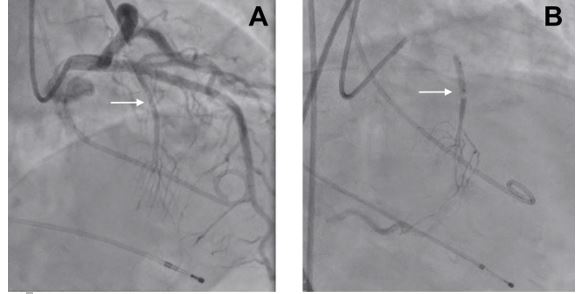

After a discussion of the case, the heart team decided to implant a transient pacemaker and perform an urgent alcohol septal ablation (ASA). The transient pacemaker was implanted in order to reduce LVOT gradients and in preparation for ASA. ASA relieves LVOTO by creating a localised myocardial infarction in the area of the basal septal muscle where SAM-septal contact is occurring. Following remodelling of this area, the LVOT is widened, thereby relieving LVOT obstruction. Previous clinical cases in the literature have shown a rapid gradient resolution and long-term improvement with ASA.

Alcohol septal ablation was performed without complications and the haemodynamic status improved with a sharp decrease in the maximum LVOT gradient (60 mmHg), and a slight elevation of blood pressure. Hours after the ablation procedure, the patient developed a complete atrioventricular block. A dual-chamber pacemaker was implanted via the left axillary route, placing the ventricular electrode in the right ventricular apex.